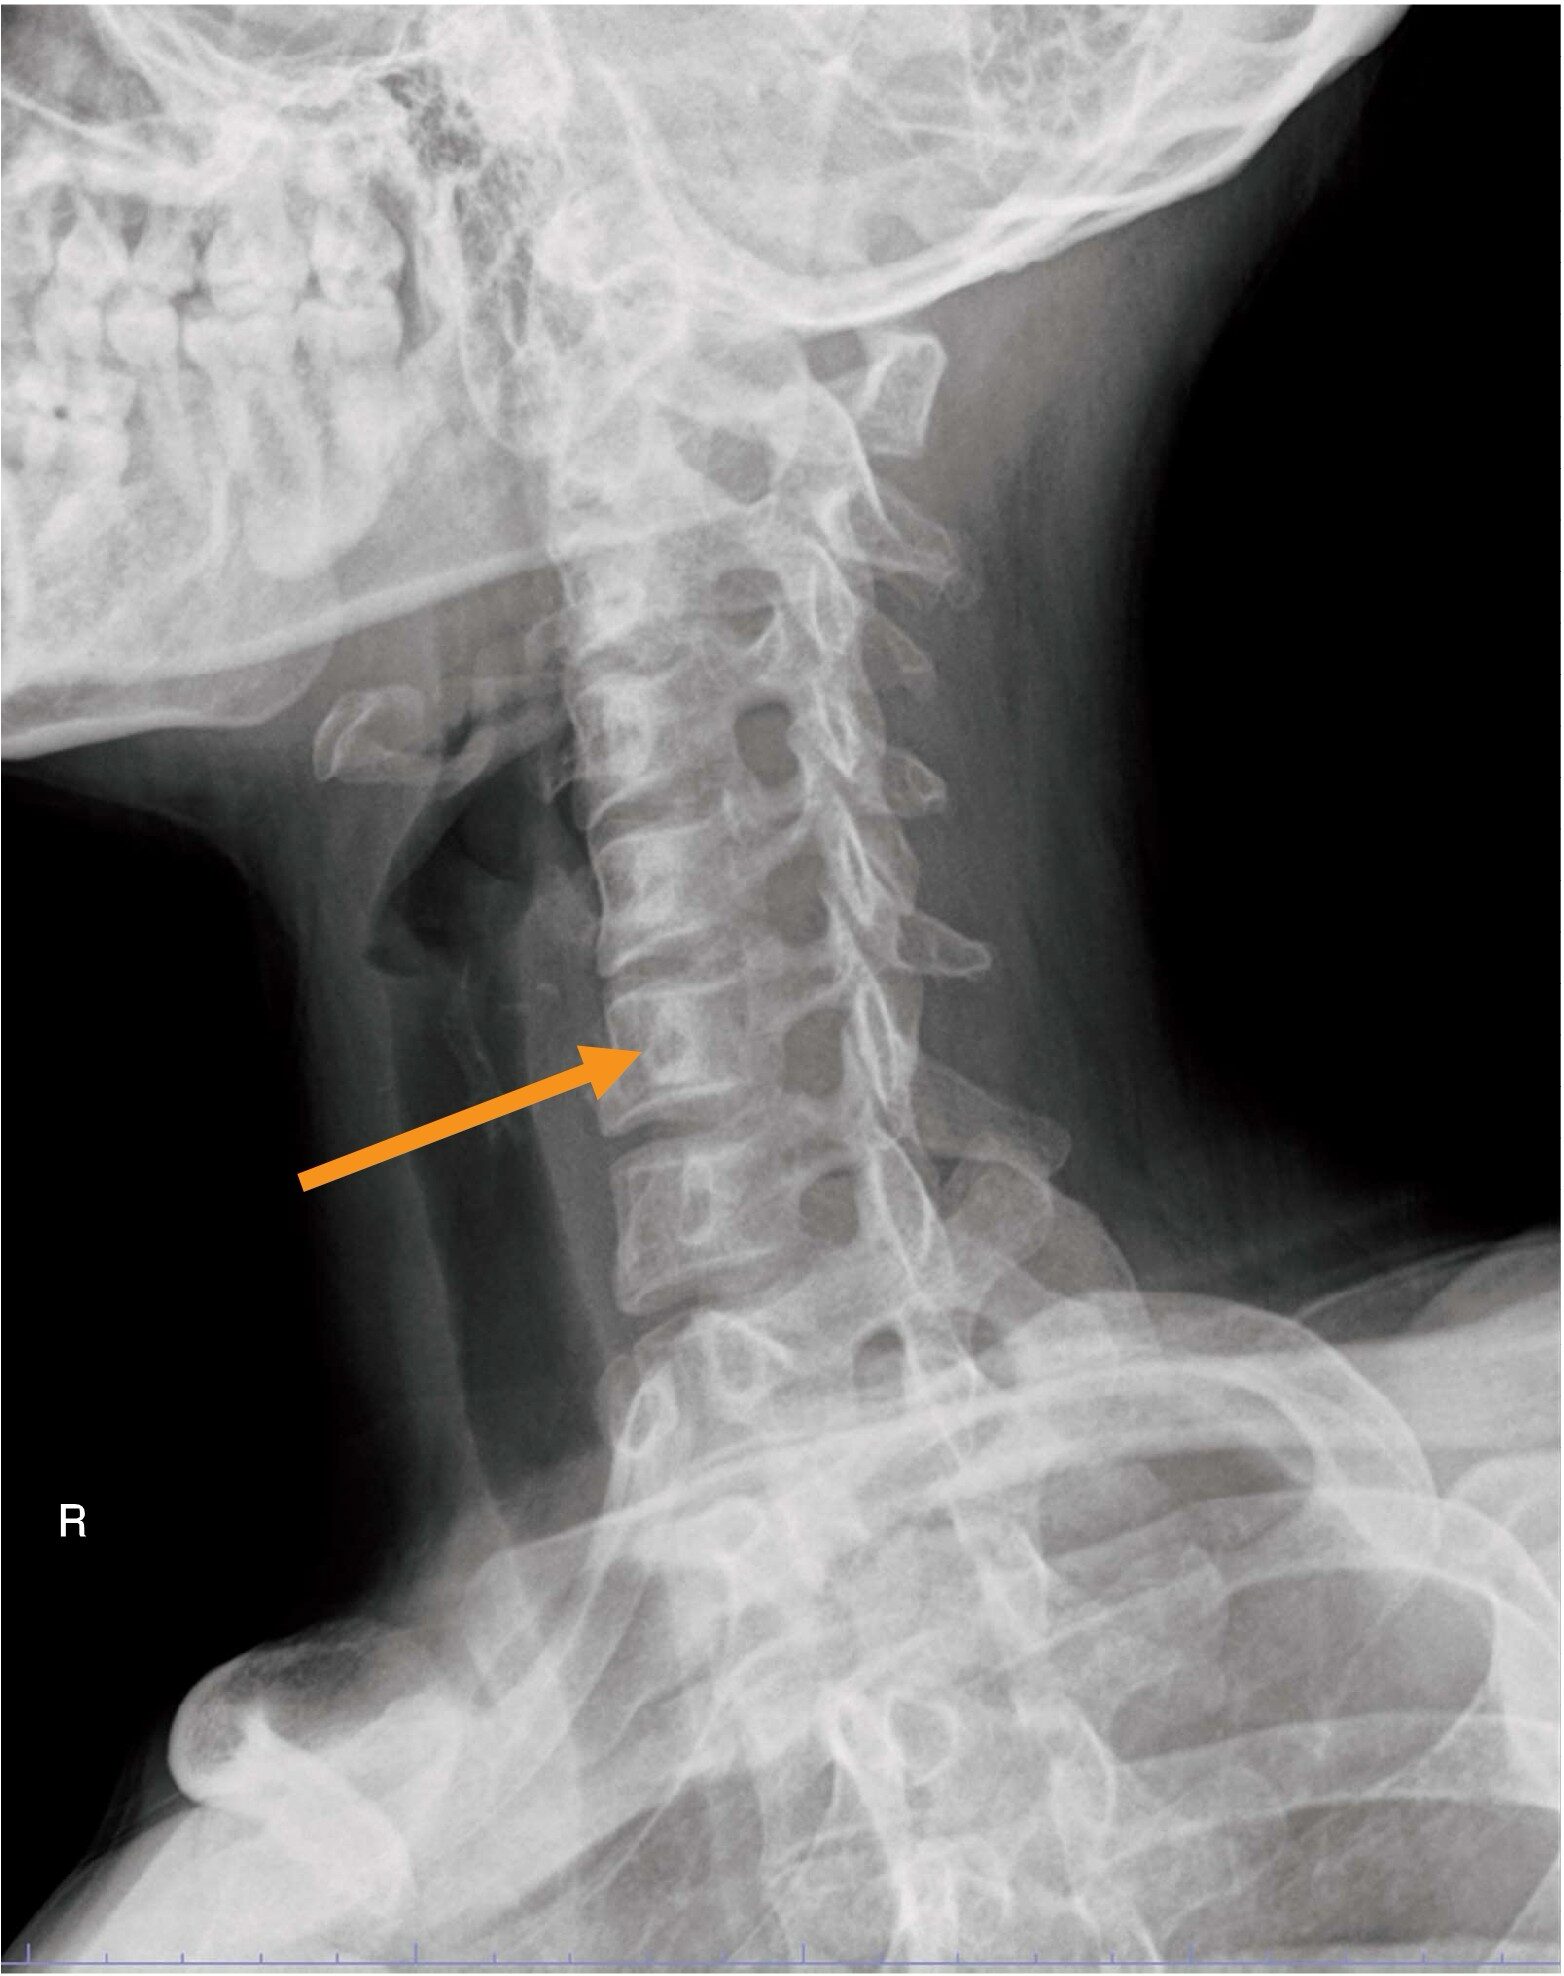

頸椎のX線写真(別冊No.9)を別に示す。矢印で示すのはどれか。

- 1棘突起

- 2椎間腔

- 3椎間孔

- 4椎弓根

- 5Luschka関節